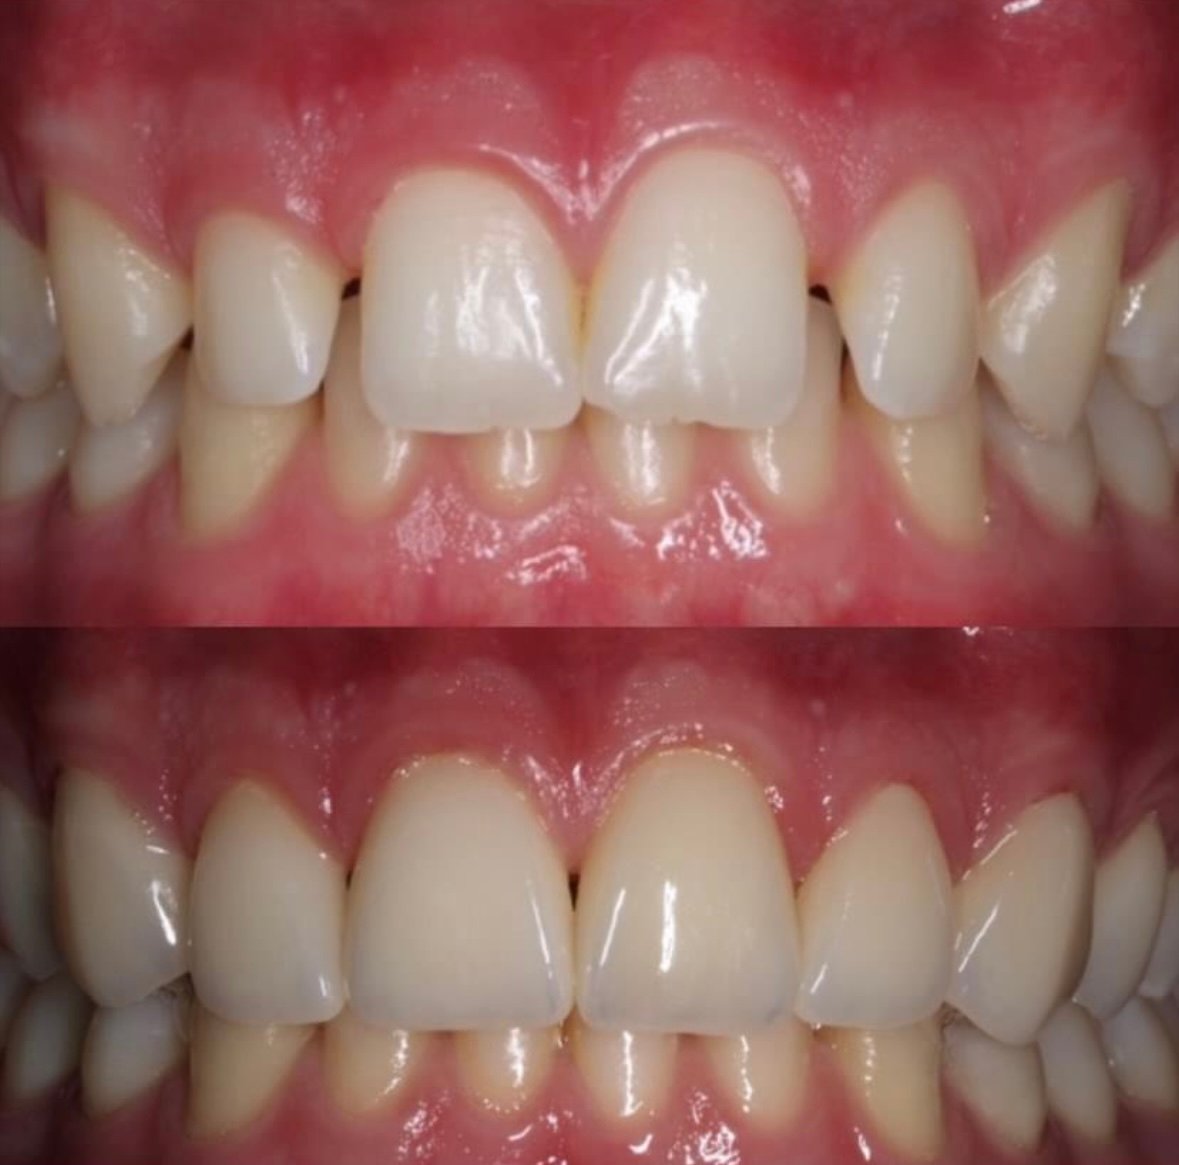

Screenshot